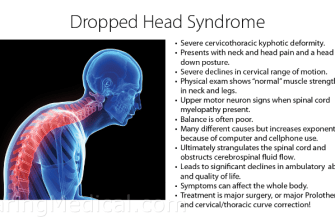

Have you ever experienced limited neck movement or